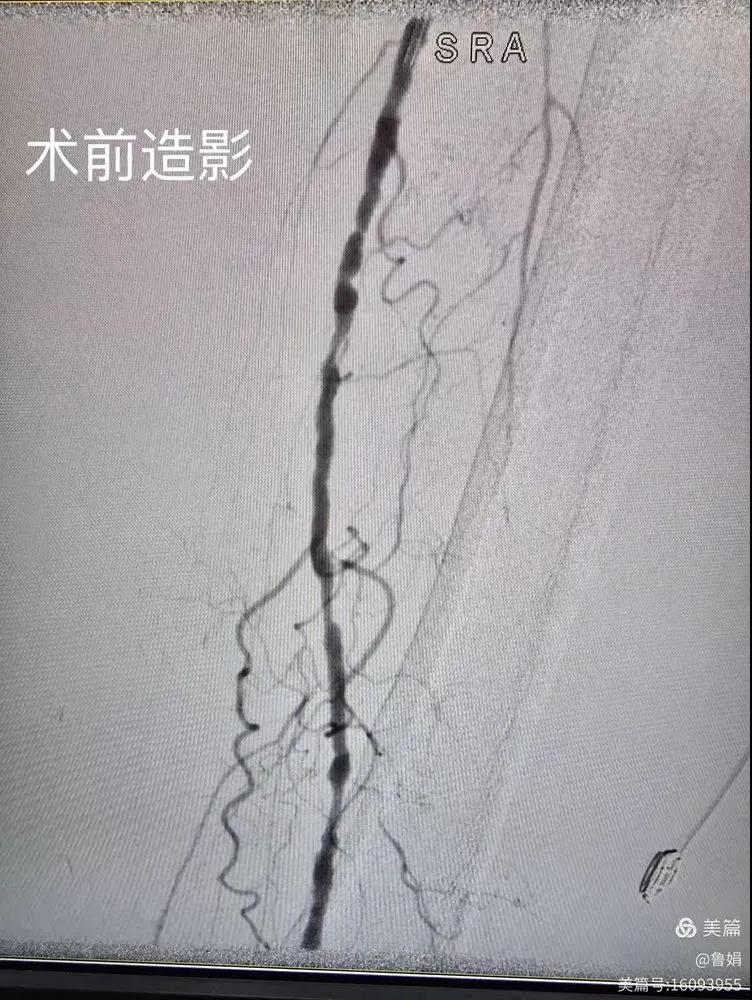

據(jù)悉,該患者,女,73歲,下肢動(dòng)脈硬化閉塞癥,“以靜息痛,間歇性跛行”入院,CTA評(píng)估:股淺動(dòng)脈,腘動(dòng)脈間斷性多段重度狹窄,外二科血管外科團(tuán)隊(duì)根據(jù)患者病情,結(jié)合檢查結(jié)果,經(jīng)過科室會(huì)診后,決定對(duì)該病人行介入治療。手術(shù)由周創(chuàng)業(yè)副主任與北大一院血管外科專家郭宏杰教授聯(lián)合開展,對(duì)股淺動(dòng)脈,腘動(dòng)脈重度閉塞段行血管開通+藥涂球囊擴(kuò)張成形,術(shù)后狹窄明顯緩解,血流恢復(fù)!